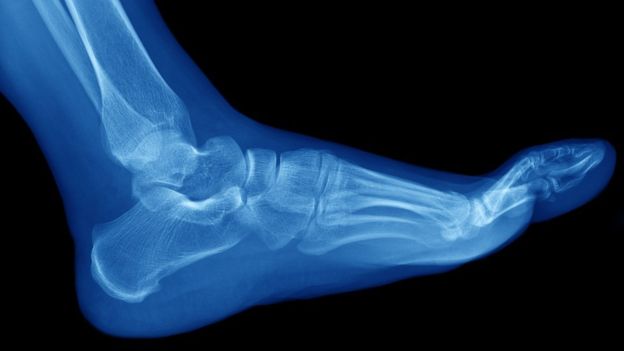

Las fracturas por estrés suelen ocurrir en los huesos de la parte inferior de la pierna y el pie, como la tibia y el peroné, los metatarsos, el talón y el tobillo. GETTY IMAGES

Este tipo de roturas están normalmente asociadas al deporte y suelen ocurrir en los huesos de la parte inferior de la pierna y el pie, como la tibia y el peroné, los metatarsos, el talón y el tobillo.